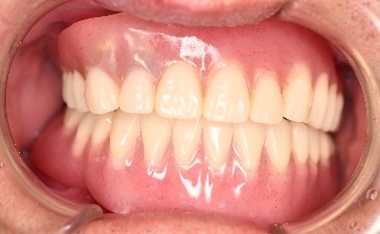

女性Iさん 60代(マグネット式入れ歯)

主訴

歯茎が腫れて、血が出ます。歯周病の治療をしてほしい。また歯をきれいにしてほしい。

治療内容

歯周病が重度に進行していました。保存することができない2本の歯を抜歯しました。歯周病の治療を徹底的にし、保存可能な9本の歯の根管治療をし、それらの歯を活用しマグネット式総入れ歯を入れました。

所感

通常の部分入れ歯にすると、入れ歯の支台になる歯は、早期に失われる可能性が高かったです。マグネット式総入れ歯は、支台になる歯に側方への力がかからないため、歯周病が進み歯の周りの骨が少なくなっている歯も効果的に活用できますし、かつ残っている歯を長持ちさせることができます。残っている歯が少なくなってきて、入れ歯で対応する場合は、マグネット式総義歯はとても良い治療法だと考えます。下顎の歯もすべて治療希望で、現在治療中です。下顎については、治療完了後に、あらためてご報告いたします。

Before

After

【義歯を装着したところ】

【義歯を外したところ】

マグネット式総入れ歯

緑丸は組み込まれたマグネット

通常の総入れ歯